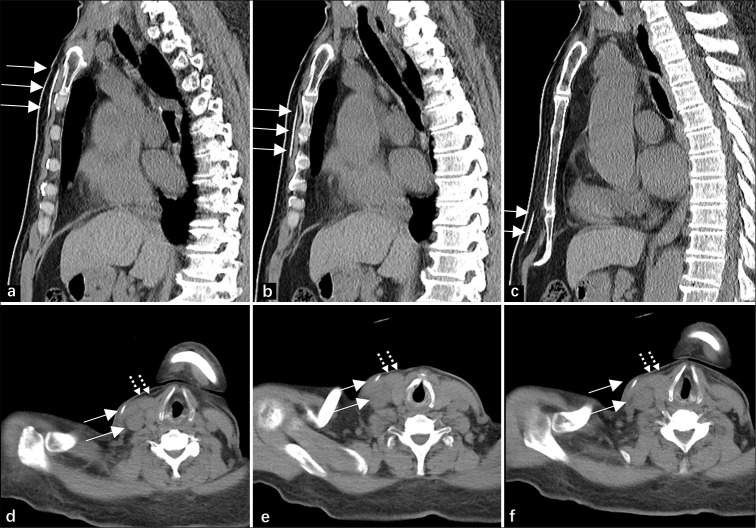

Ventriculoperitoneal (VP) shunts are commonly used to treat hydrocephalus by diverting cerebrospinal fluid from the ventricles to the peritoneal cavity. Migration of the VP shunt into the heart and pulmonary artery is a rare complication. Herein, we described a 67-year-old man with a VP shunt catheter that migrated through the venous system into the pulmonary circulation, highlighting early diagnosis with imaging and symptoms.

脑室-腹膜(VP)分流术通常用于脑积水的治疗,将脑脊液从脑室转移到腹膜腔。副静脉分流移入心脏和肺动脉是一种罕见的并发症。在此,我们描述了一位67岁的男性患者,他的VP分流导管通过静脉系统进入肺循环,强调了早期诊断的影像学和症状。